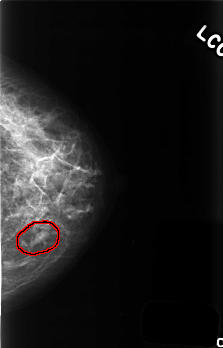

FILE: C_0507_1.LEFT_CC.OVERLAY

TOTAL_ABNORMALITIES 1

ABNORMALITY 1

LESION_TYPE MASS SHAPE LOBULATED MARGINS CIRCUMSCRIBED

ASSESSMENT 3

SUBTLETY 5

PATHOLOGY BENIGN

TOTAL_OUTLINES 1

BOUNDARY